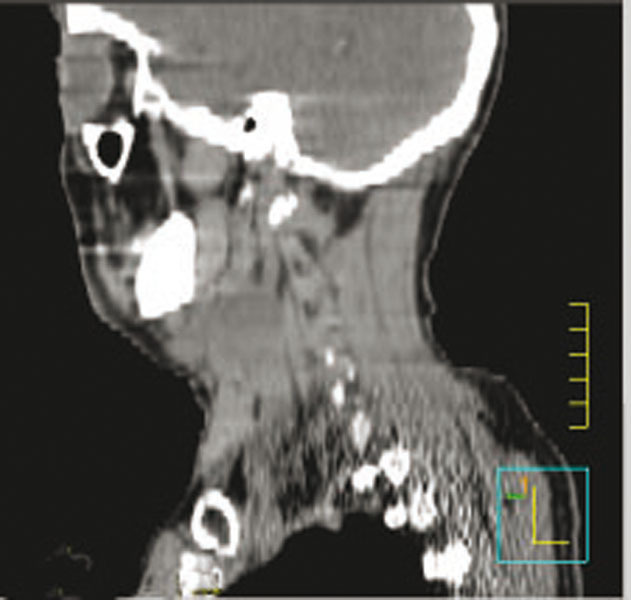

TDM simple : carcinome épidermoïde du sinus piriforme gauche avec une adénopathie tumorale nécrosée sous-digastrique gauche.